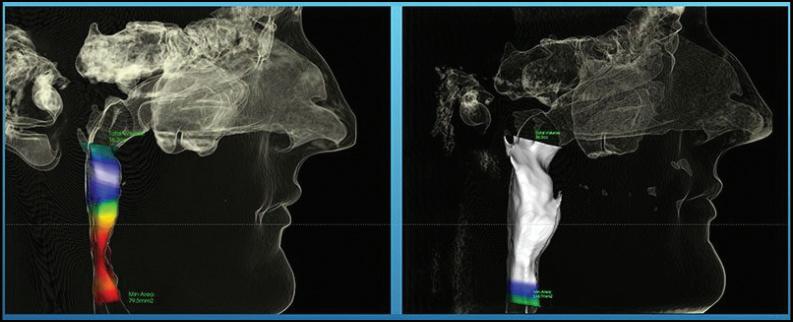

By Jeffrey L. Brown, DDS Sleep & TMJ Therapy

In the world of TMD (temporomandibular disorder), there are many ways to treat the problem, but it must always begin with a good diagnosis. First and foremost are an MRI and CBCT x-ray of the joints and surrounding areas. The MRI is a magnetic imaging device that looks directly at the discs in the jaw joints. This high-

tech machine looks inside the joints and produces soft tissue images to help with your diagnosis. The CBCT is the x-ray machine that uses low-dose radiation to look at the bones inside the skull, the cervical spine, the teeth, and the condyles. These tools are what we use to come up with a diagnosis and then a plan to help you get better.

In the world of TMD (temporomandibular treat the problem, but it must always foremost are an MRI and CBCT x-ray MRI is a magnetic imaging device that joints. This high-tech machine looks images to help with your diagnosis. low-dose radiation to look at the bones teeth, and the condyles. These tools diagnosis and then a plan to help you